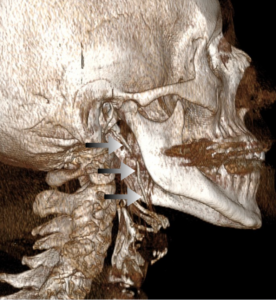

- 3D Αξονική Τομογραφία (CT) σπλαχνικού κρανίου: Θεωρείται η εξέταση εκλογής (gold standard), καθώς επιτρέπει την ακριβή μέτρηση του μήκους της απόφυσης και τον προσδιορισμό της γωνίας της σε σχέση με τις γύρω δομές.